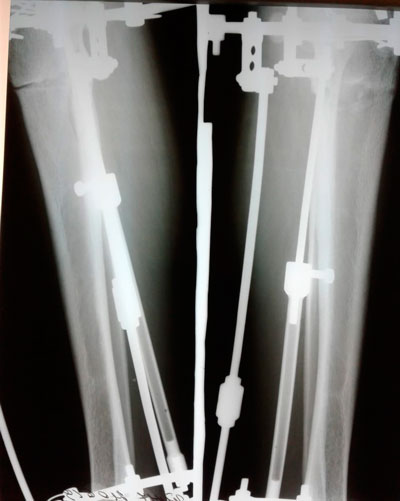

Дата операции - 19.04.2019г.

Дата снятия аппаратов - 26.07.2019г.

Срок сращения - 96 дней.

Добрый день. У меня вопрос меня волнующий возник. Смотрите, у парня сразу после снятия коленки очень впритык друг к другу , хоть и стопы он поставил не вместе, ну пол сантиметра между ними есть. А вот спустя 6 месяцев коленки уже с щелью стали , стопы впритык. Ноги проседают немного???? Мальчику то это красиво, а вот мне как девочке этого совсем не хочется.

Здравствуйте! Отёк уходит, ось на месте!